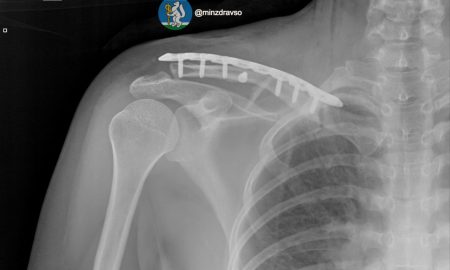

Врачи смогли сохранить возможность ходить Врачи екатеринбургской травматологической больницы № 36 вернули к жизни 44-летнюю женщину после жуткой аварии, сообщает Министерство здравоохранения Свердловской области....